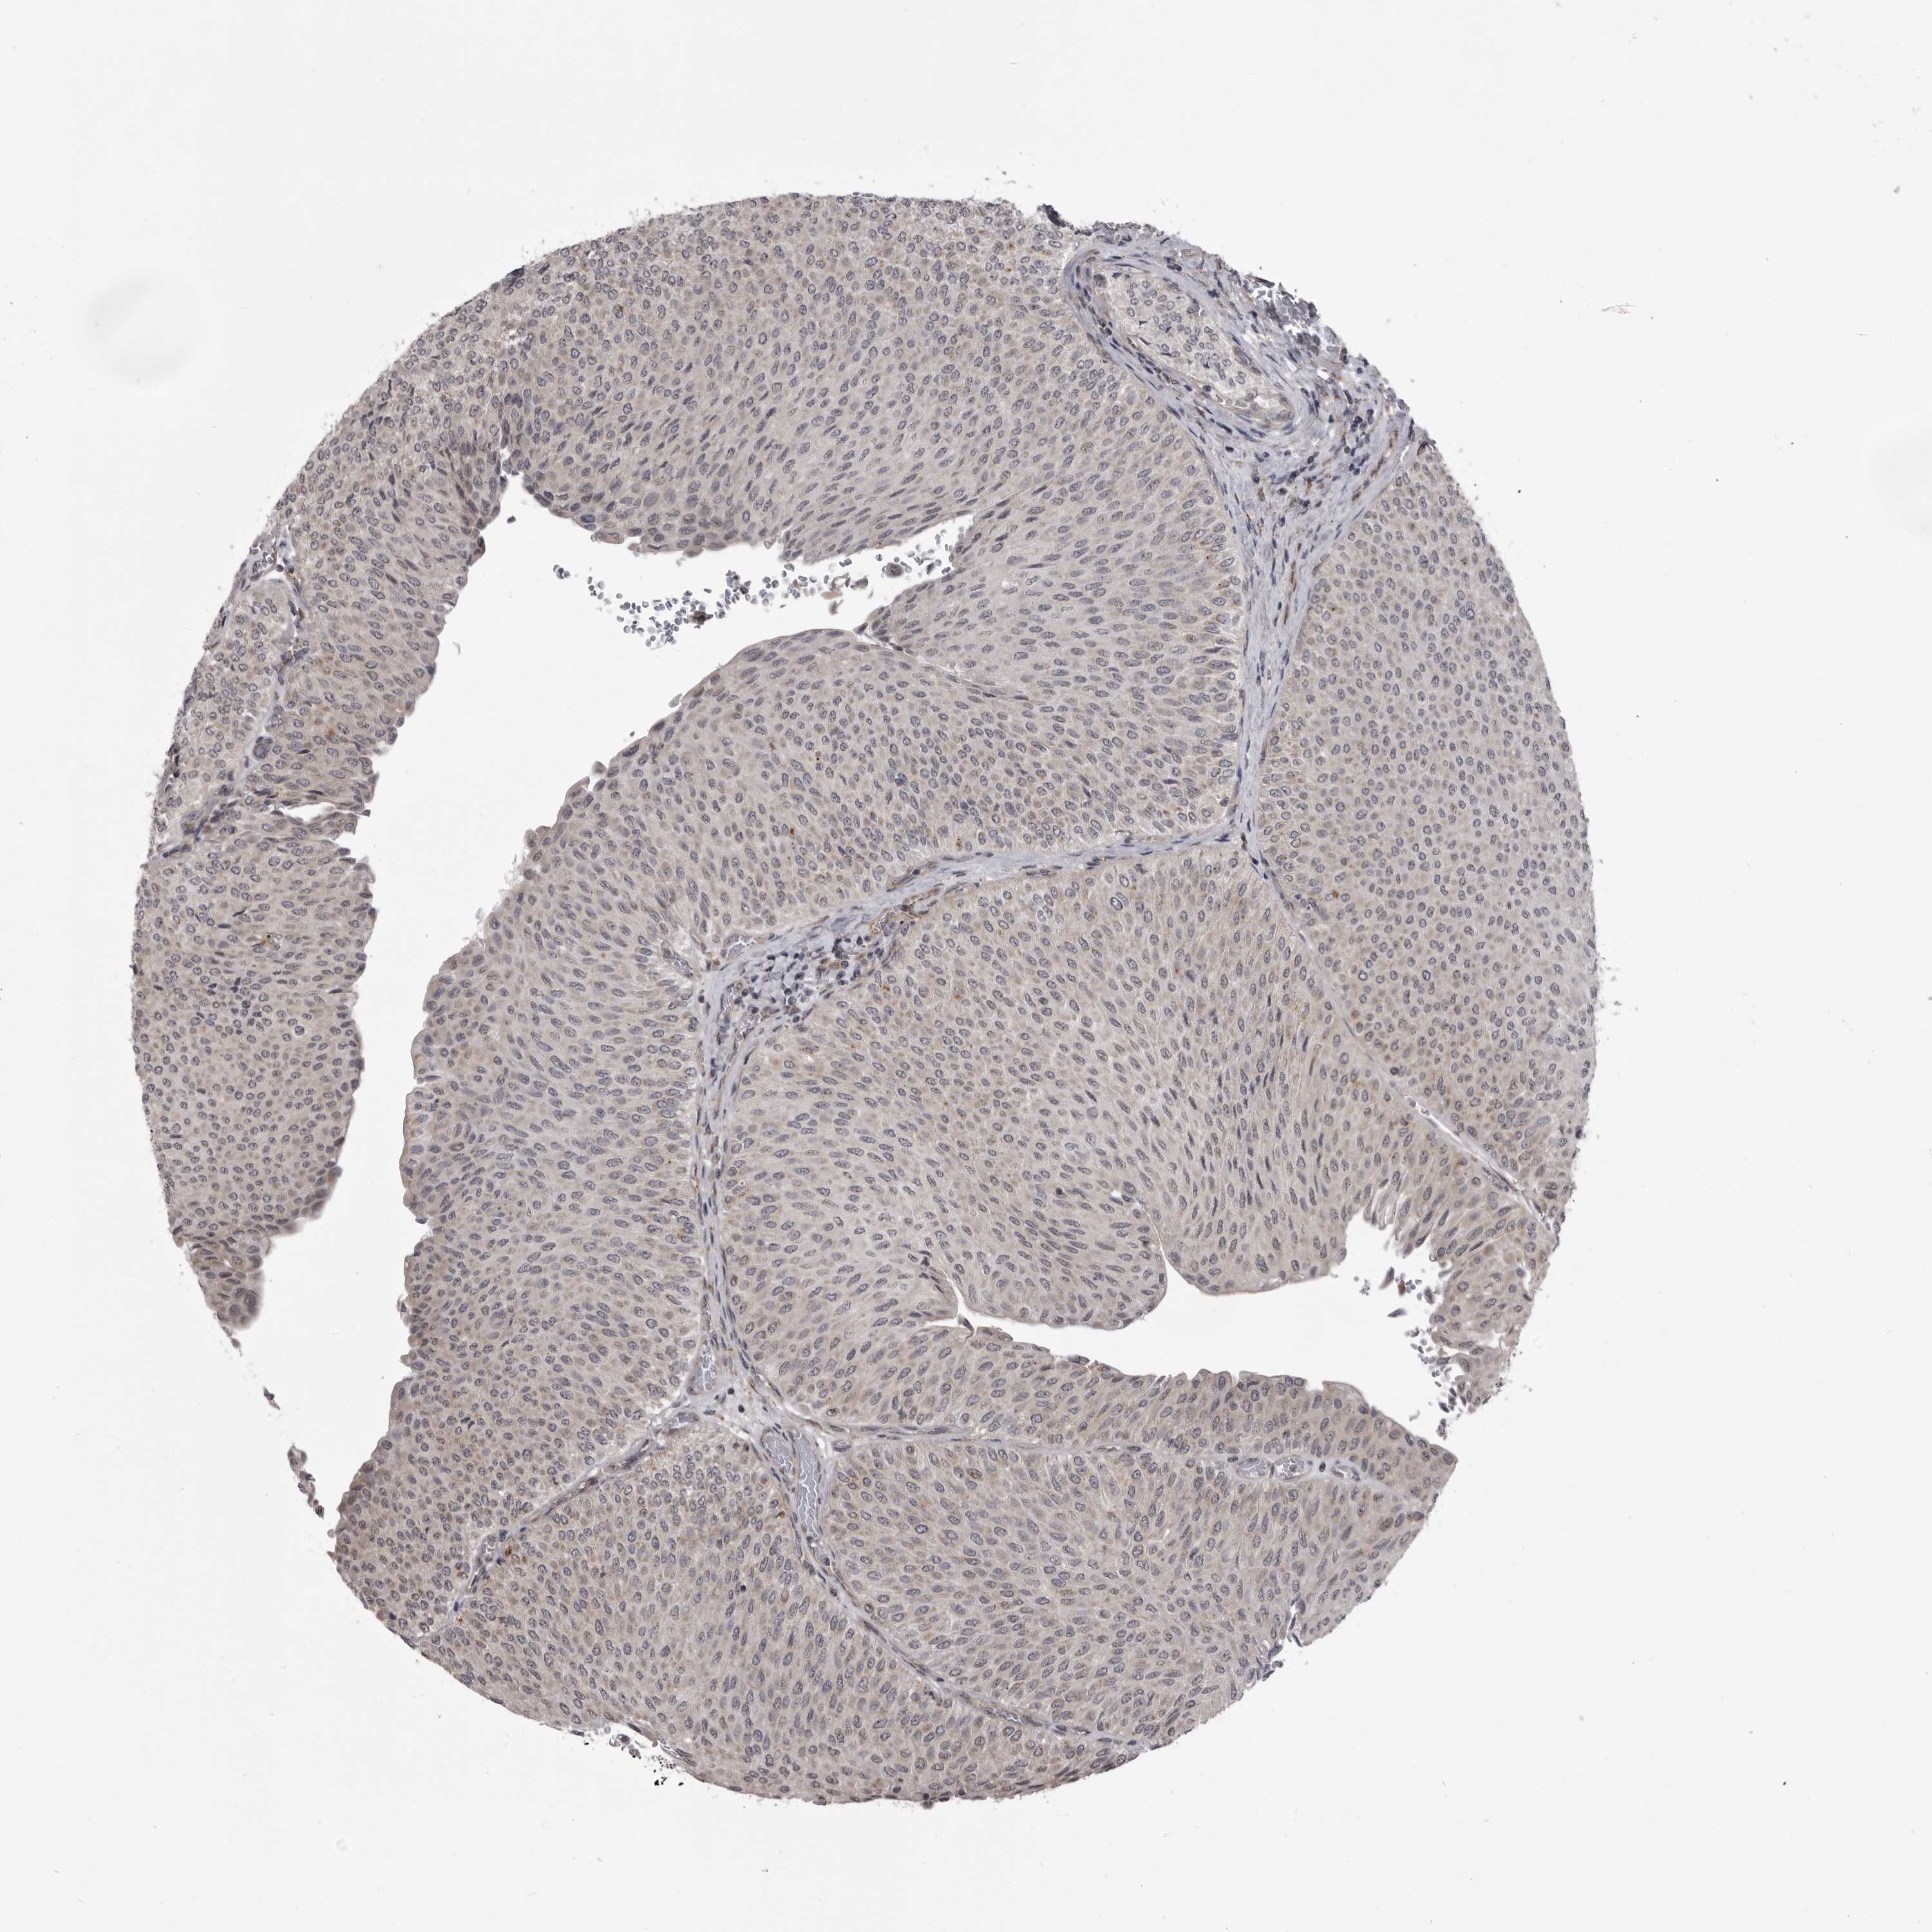

UROTHELIAL CANCER - Protein expressioni

A mouse-over function shows sample information and annotation data. Click on an image to view it in a full screen mode. Samples can be filtered based on level of antibody staining by selecting one or several of the following categories: high, medium, low and not detected. The assay and annotation is described here.

Note that samples used for immunohistochemistry by the Human Protein Atlas do not correspond to samples in the TCGA dataset.

Antibody stainingi

Antibody staining in the annotated cell types in the current human tissue is reported as not detected, low, medium, or high, based on conventional immunohistochemistry profiling in selected tissues. This score is based on the combination of the staining intensity and fraction of stained cells.

Each image is clickable and will lead to virtual microscopy that enables deeper exploration of all samples and also displays staining intensity scores, fraction scores and subcellular localization as well as patient and tissue information for each sample.

Antibody HPA024730

Antibody HPA024731

Antibody HPA024817

Staining

High

Medium

Low

Not detected

Intensity

Strong

Moderate

Weak

Negative

Quantity

>75%

75%-25%

<25%

None

Location

Nuclear

Cytoplasmic/membranous

Cytoplasmic/membranous,nuclear

Urothelial carcinoma, Low grade

Urothelial carcinoma, High grade